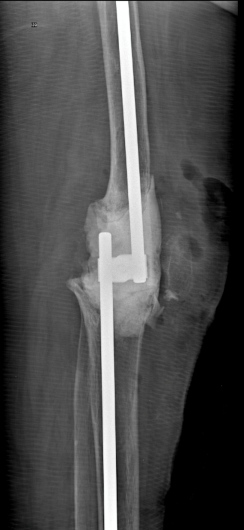

Practico una ortopedia centrada en usted como paciente, moderna, mínimamente invasiva y basada en evidencia científica. Me mantengo en constante actualización nacional e internacional y estoy certificado en cirugía de reemplazo articular con asistencia robótica con el sistema Mako® de Stryker, una tecnología de última generación para el reemplazo de cadera y rodilla, la más avanzada de Latinoamérica y el mundo.

Gracias a la planificación quirúrgica en modelos tridimensionales personalizados, este sistema permite una precisión milimétrica, lo que se traduce en:

Mayor estabilidad de la prótesis

Recuperación funcional más rápida

Para lograr los mejores resultados, realizo mis procedimientos quirúrgicos en el Hospital Internacional de Colombia (HIC). Esta institución cuenta con la acreditación de la Joint Commission International (JCI), un sello de excelencia que solo poseen los mejores hospitales del mundo y que garantiza que usted recibirá atención bajo los más estrictos estándares globales de seguridad y calidad hospitalaria.

Artroplastia de la rodilla